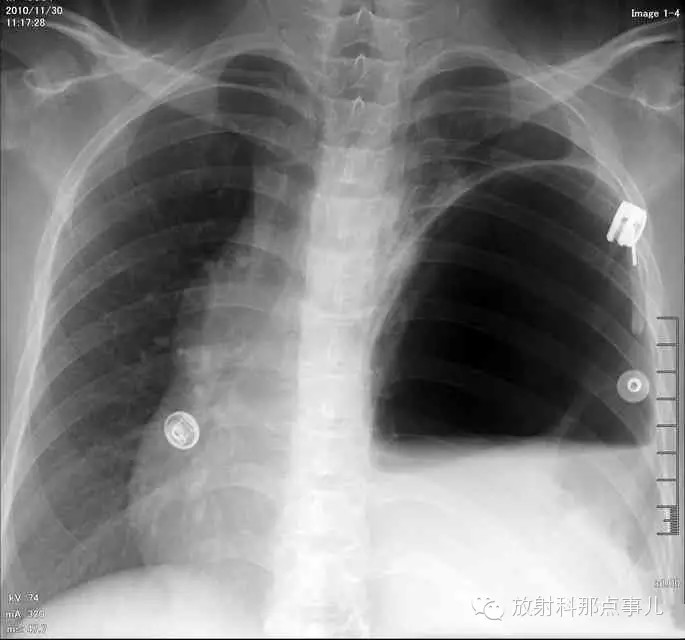

门诊腹部透视发现左侧胸腔巨大气液平面,为排除膈疝口服钡剂,但造影剂未见进入胃内。嘱住院,外科给予胃肠减压、补液等处理常规处理(未引流出明显气、液体)。5个半小时后再次检查,见少量造影剂进入消化道;为进一步了解情况,予泛影葡胺分别经胃管推注及口服,但均未进入胃内。当天进行外科急诊手术。

更正:检查时间在左上方。

大部分胃、脾及横结肠均经过胸肋三角疝入左侧胸腔内,并见疝环形成。